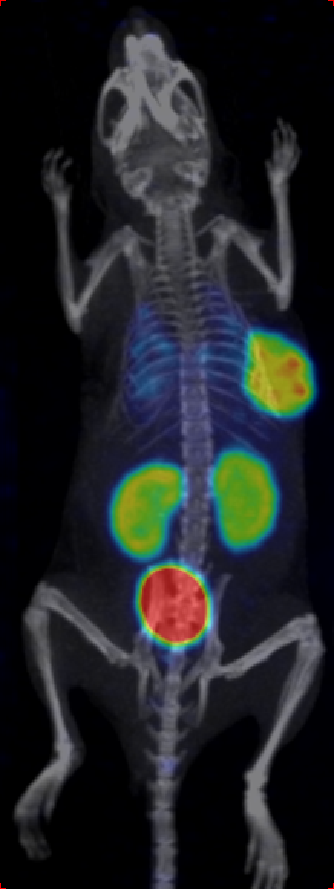

Through quality and process explorations with Zr-89-marked antibody conjugates, highly emissive-pure radiodiagnostic drug molecules are obtained and supplied for preclinical animal imaging and biodistribution studies, as well as subsequent IIT imaging in the clinic.

Rapid validation of Zr-89-marked antibodies

Fast lesion cumulation, most efficient distribution and high targeting ability for xenotransplanted tumor models.